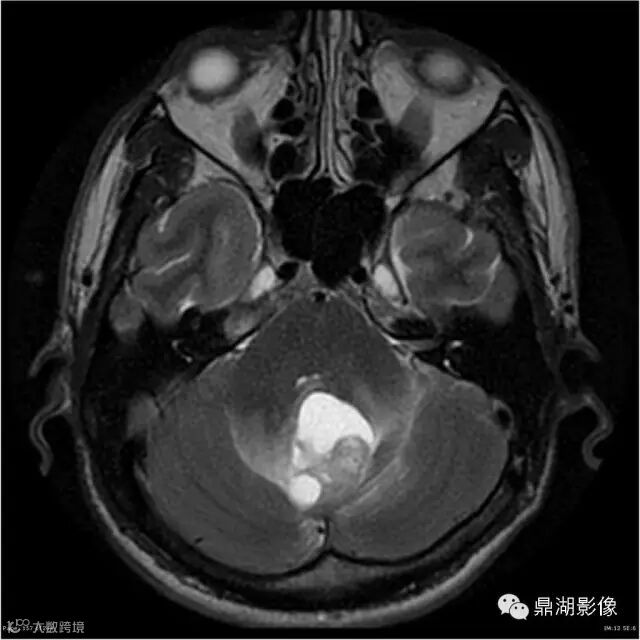

Axial T2WI

影像:可见一个约43 x 36 x 31mm的从小脑蚓部延伸而来的占位,T1WI、T2WI呈高低混杂信号,病灶周边见流空血管影及水肿带,增强病灶明显强化,中心见无明显坏死区,它紧靠左小脑幕上。第四脑室受压变窄,室管膜水肿,可见脑桥及延脑扁桃体进入枕骨大孔。

本例为一例实质性血管母细胞瘤。实性血管母细胞瘤CT平扫示病灶呈等或高密度,增强后可见明显强化。MRI平扫通常病灶很不均质,T1呈稍低信号为主的较混杂信号,T2呈等、高信号,DWI通常呈低信号或等信号。文献报道,实性血管母细胞瘤较典型的表现为瘤内及瘤周扩张的流空血管影,瘤周中、重度水肿。因此,小脑半球区的单发肿块伴流空血管影,周围大片水肿以及增强后肿块明显强化"形态规则"边界清楚,此时应将实性血管母细胞瘤考虑在内。